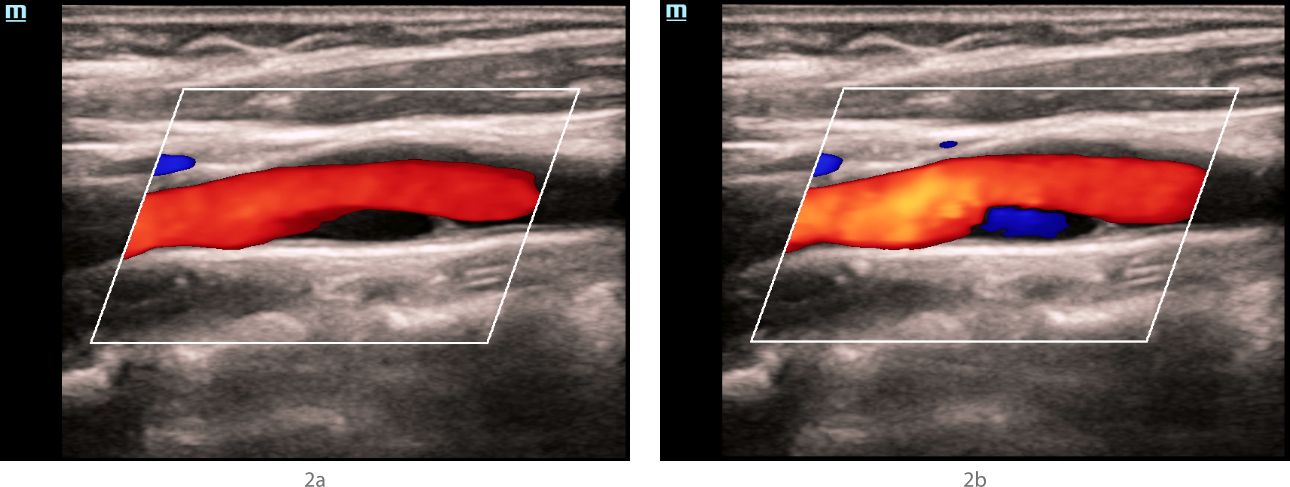

Ultrasound examination ŌĆō Doppler modes

In the mode of color Doppler mapping, in the bifurcation of the left common carotid artery along the posterior wall, an anechoic zone with a smooth surface, about 1 cm long, was visualized (Fig. 2a), which was partially filled with blue blood flow (as opposed to red in the rest of the carotid arteries) (Fig. 2b). The "aliasing" effect over the zone of detected changes was not detected. In the spectral Doppler mode, in the bifurcation of the common carotid artery, the velocity parameters of blood flow were within normal limits, no areas with local changes in hemodynamics were detected (Fig. 3).

In the bifurcation of the common carotid artery along the posterior wall, an anechoic structure is visualized, having a hyperechoic contour in the proximal shoulder, and partially filled with blue blood flow during different phases of the cardiac cycle and when the device settings are changed.

The results of ultrasound in the FSBI NCN. According to seroscale and Doppler ultrasound modes, hyperechoic linear structures were detected in the bifurcation of the common carotid arteries on both sides, with a large narrowing of the vessel lumen on the left, which could be a sign of intimal detachment and suggest dissection or a local form of fibromuscular dysplasia. An anechoic staining defect of the vessel lumen was detected behind the hyperechoic structure in the distal direction on the left in the CDK mode, which was partially filled with the color (blue) opposite to the main flow direction when changing the settings of the device and the phase of the cardiac cycle. Since it was not possible to completely paint the anechoic defect with a color stream, while not flooding the lumen of the common carotid artery with adjacent structures with color, it was impossible to exclude the presence of an atherosclerotic plaque in a typical place of its formation with a tire visualized in its proximal part or, but less likely, a parietal thrombus. The absence of an increase in the rate of blood flow and local changes in hemodynamics indicated the hemodynamic insignificance of structural changes in the carotid arteries on both sides.